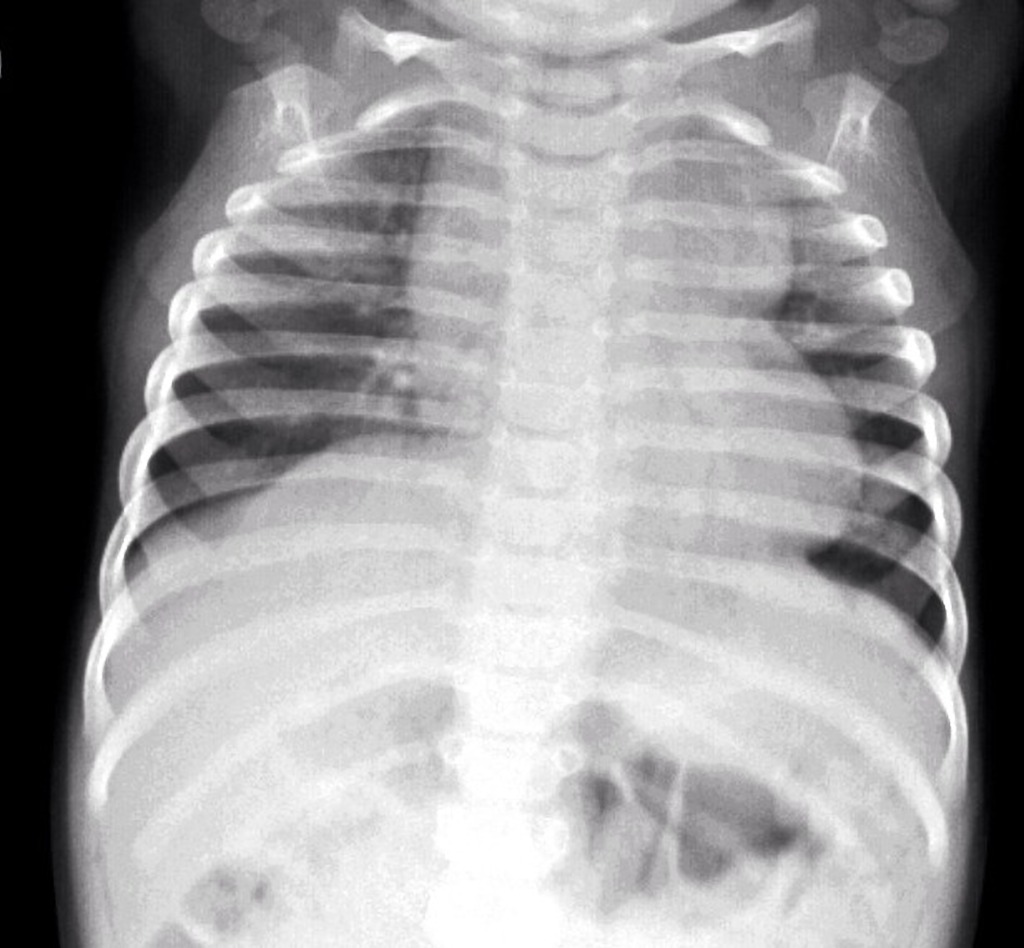

- Chest radiograph may show classic “egg of a string”

- EKG is non-diagnostic